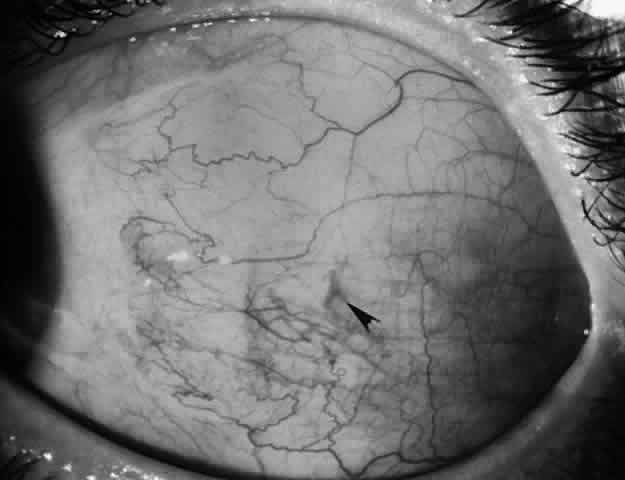

Reintervention to correct strabismus is indicated if a technical problem occurred immediately after the initial procedure. A muscle that has become disinserted or is “lost” postoperatively requires immediate exploration and correction of the problem (Figs. 2 and 3). A similar situation may occur when a previously operated muscle retracts ("slips") inside the muscle capsule (Fig. 4). The slipped muscle will appear paretic, and early surgical intervention should be considered. The clinical pictures of these technical failures are very similar. There is poor function of the affected rectus muscle, and the induced strabismus will be noncomitant. Operations may be performed on the incorrect eye muscles or eye (Fig. 5). If this occurs, reoperation should not be delayed.

Fig. 2. This 8-year-old patient had her lateral rectus recessed 4 days before referral. Twenty-five prism diopters of esotropia and absent abduction were noted. The insertion was “empty” in appearance, and an untied suture could be visualized underneath the conjunctiva (arrow).